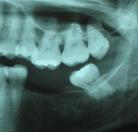

Otra causa que puede afectar a la posición dental es la ausencia de algún diente, generalmente por su extracción. Esto hace que los dientes que están próximos a la ausencia tiendan a ocupar ese espacio, y de la misma manera el diente antagonista, es decir el que se opone al masticar, tienda a erupcionar o a "crecer" y de la misma manera a ocupar parte del espacio del diente que falta.

Los dientes restantes pueden sufrir migraciones como ya comentamos, y estar sujetos a un mayor desgaste y movilidad como consecuencia de su sobrecarga funcional. Las articulaciones temporomandibulares también pueden verse afectadas como consecuencia de la pérdida de dientes.